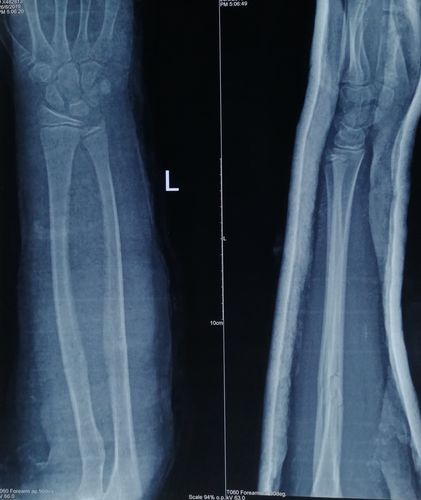

青枝骨折图片,青枝骨折

小儿桡骨远端青枝骨折

对于小孩尺桡骨青枝骨折,切勿暴力复位,慢工出细活,同样可以达到

儿童桡骨青枝骨折图片